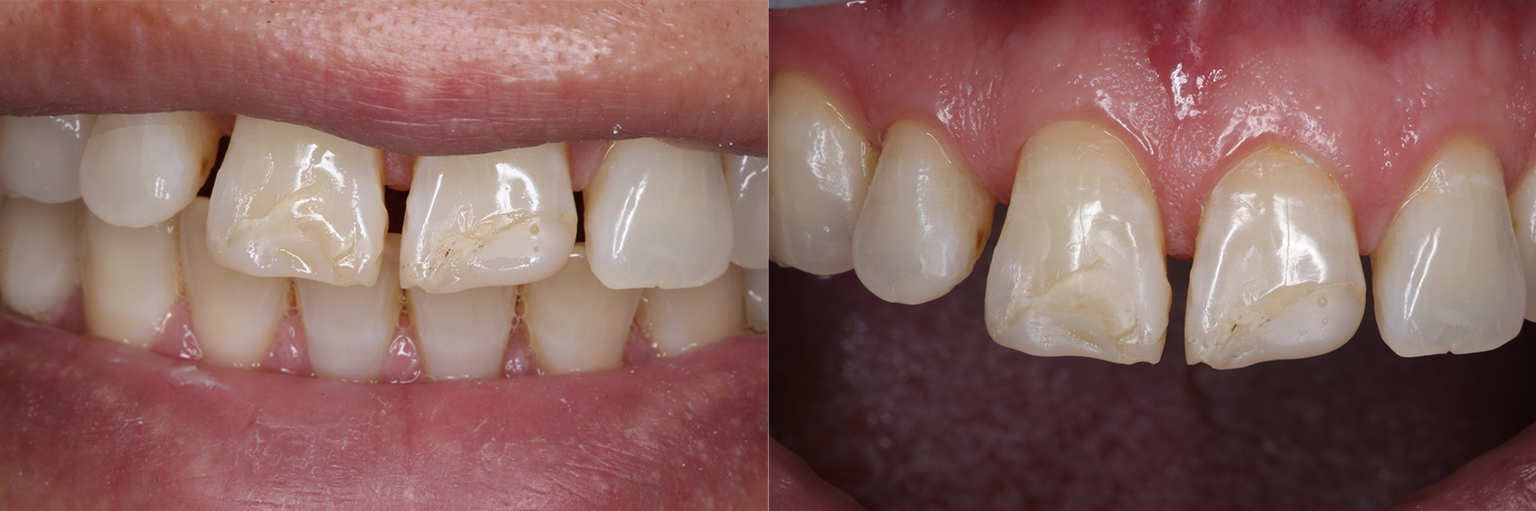

前歯を綺麗にしたい

- 相談内容

- 前歯を綺麗にしたい

- 患者情報

- 40代男性

- 治療前の状態

- 空隙歯列(すきっぱ)、歯牙形態の不整

- 治療内容

- ホワイトニング・ラミネートベニア

- 治療期間

- 4ヶ月

定期検診で噛み合わせをチェックする必要があり、調整を行うこともあります。噛み合わせの調整に費用はかかりません。メンテナンスが甘い場合、セラミックが欠けたり破損したりすることがあります。

ホワイトニングはほとんどの方が歯を白く明るく変化させることができますが、ごく稀にあまり変化が見られない場合もあります。この方は問題ありませんでした。